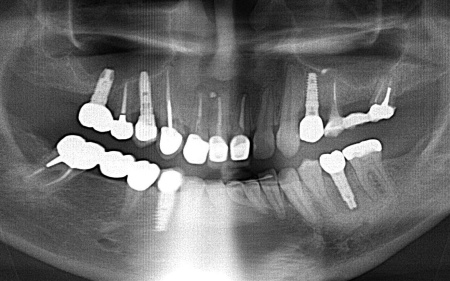

| 診断 | 拝見したところ、左上奥歯(第1小臼歯)は歯の上の部分である歯冠が折れ、歯根のみ残っている状態でした。 また、左下奥歯(第2小臼歯)には被せ物が装着されています。 レントゲン撮影をして痛みの原因を詳しく検査したところ、左上下奥歯の歯根が割れており、その影響で痛みが出ていると考えられました。 歯根が割れた歯は温存が難しく、このまま放置すると炎症が広がって周囲の歯に悪影響を及ぼすおそれがあるため、抜歯せざるを得ない場合があります。 以上のことから、温存が難しいと判明している左上奥歯は抜き、左下奥歯は被せ物を取り外して内部を確認したうえで、適切な処置を行うことが望ましいと診断しました。 |

| 行ったご提案・治療内容 | 診断結果をお伝えし、患者様の了承を得たうえで左下奥歯の被せ物を外したところ、レントゲン検査での診断どおり、歯根が割れていることが確認できました。 そのため、患者様には左上下奥歯とも温存が難しい旨を説明し、抜歯に同意いただきました。 患者様は、以前当院で人工歯根を顎の骨に埋入して歯を装着するインプラント治療を受けていたため、今回も左上下奥歯ともインプラント治療を希望されています。 メリット デメリット 改めてメリットとデメリットをしっかりお伝えしたところ、インプラント治療に対する不安はないとのことで、治療に同意いただきました。 まず、左上下奥歯を慎重に抜きます。 インプラント手術後は経過観察を行い、インプラントが顎の骨に結合したことを確認したら、インプラント上部に取り付ける人工歯を作製するために精密な型取りを実施します。 後日、完成した人工歯をインプラントに装着し、使用感や見た目に問題がないことを確認して、治療を終了しました。 |